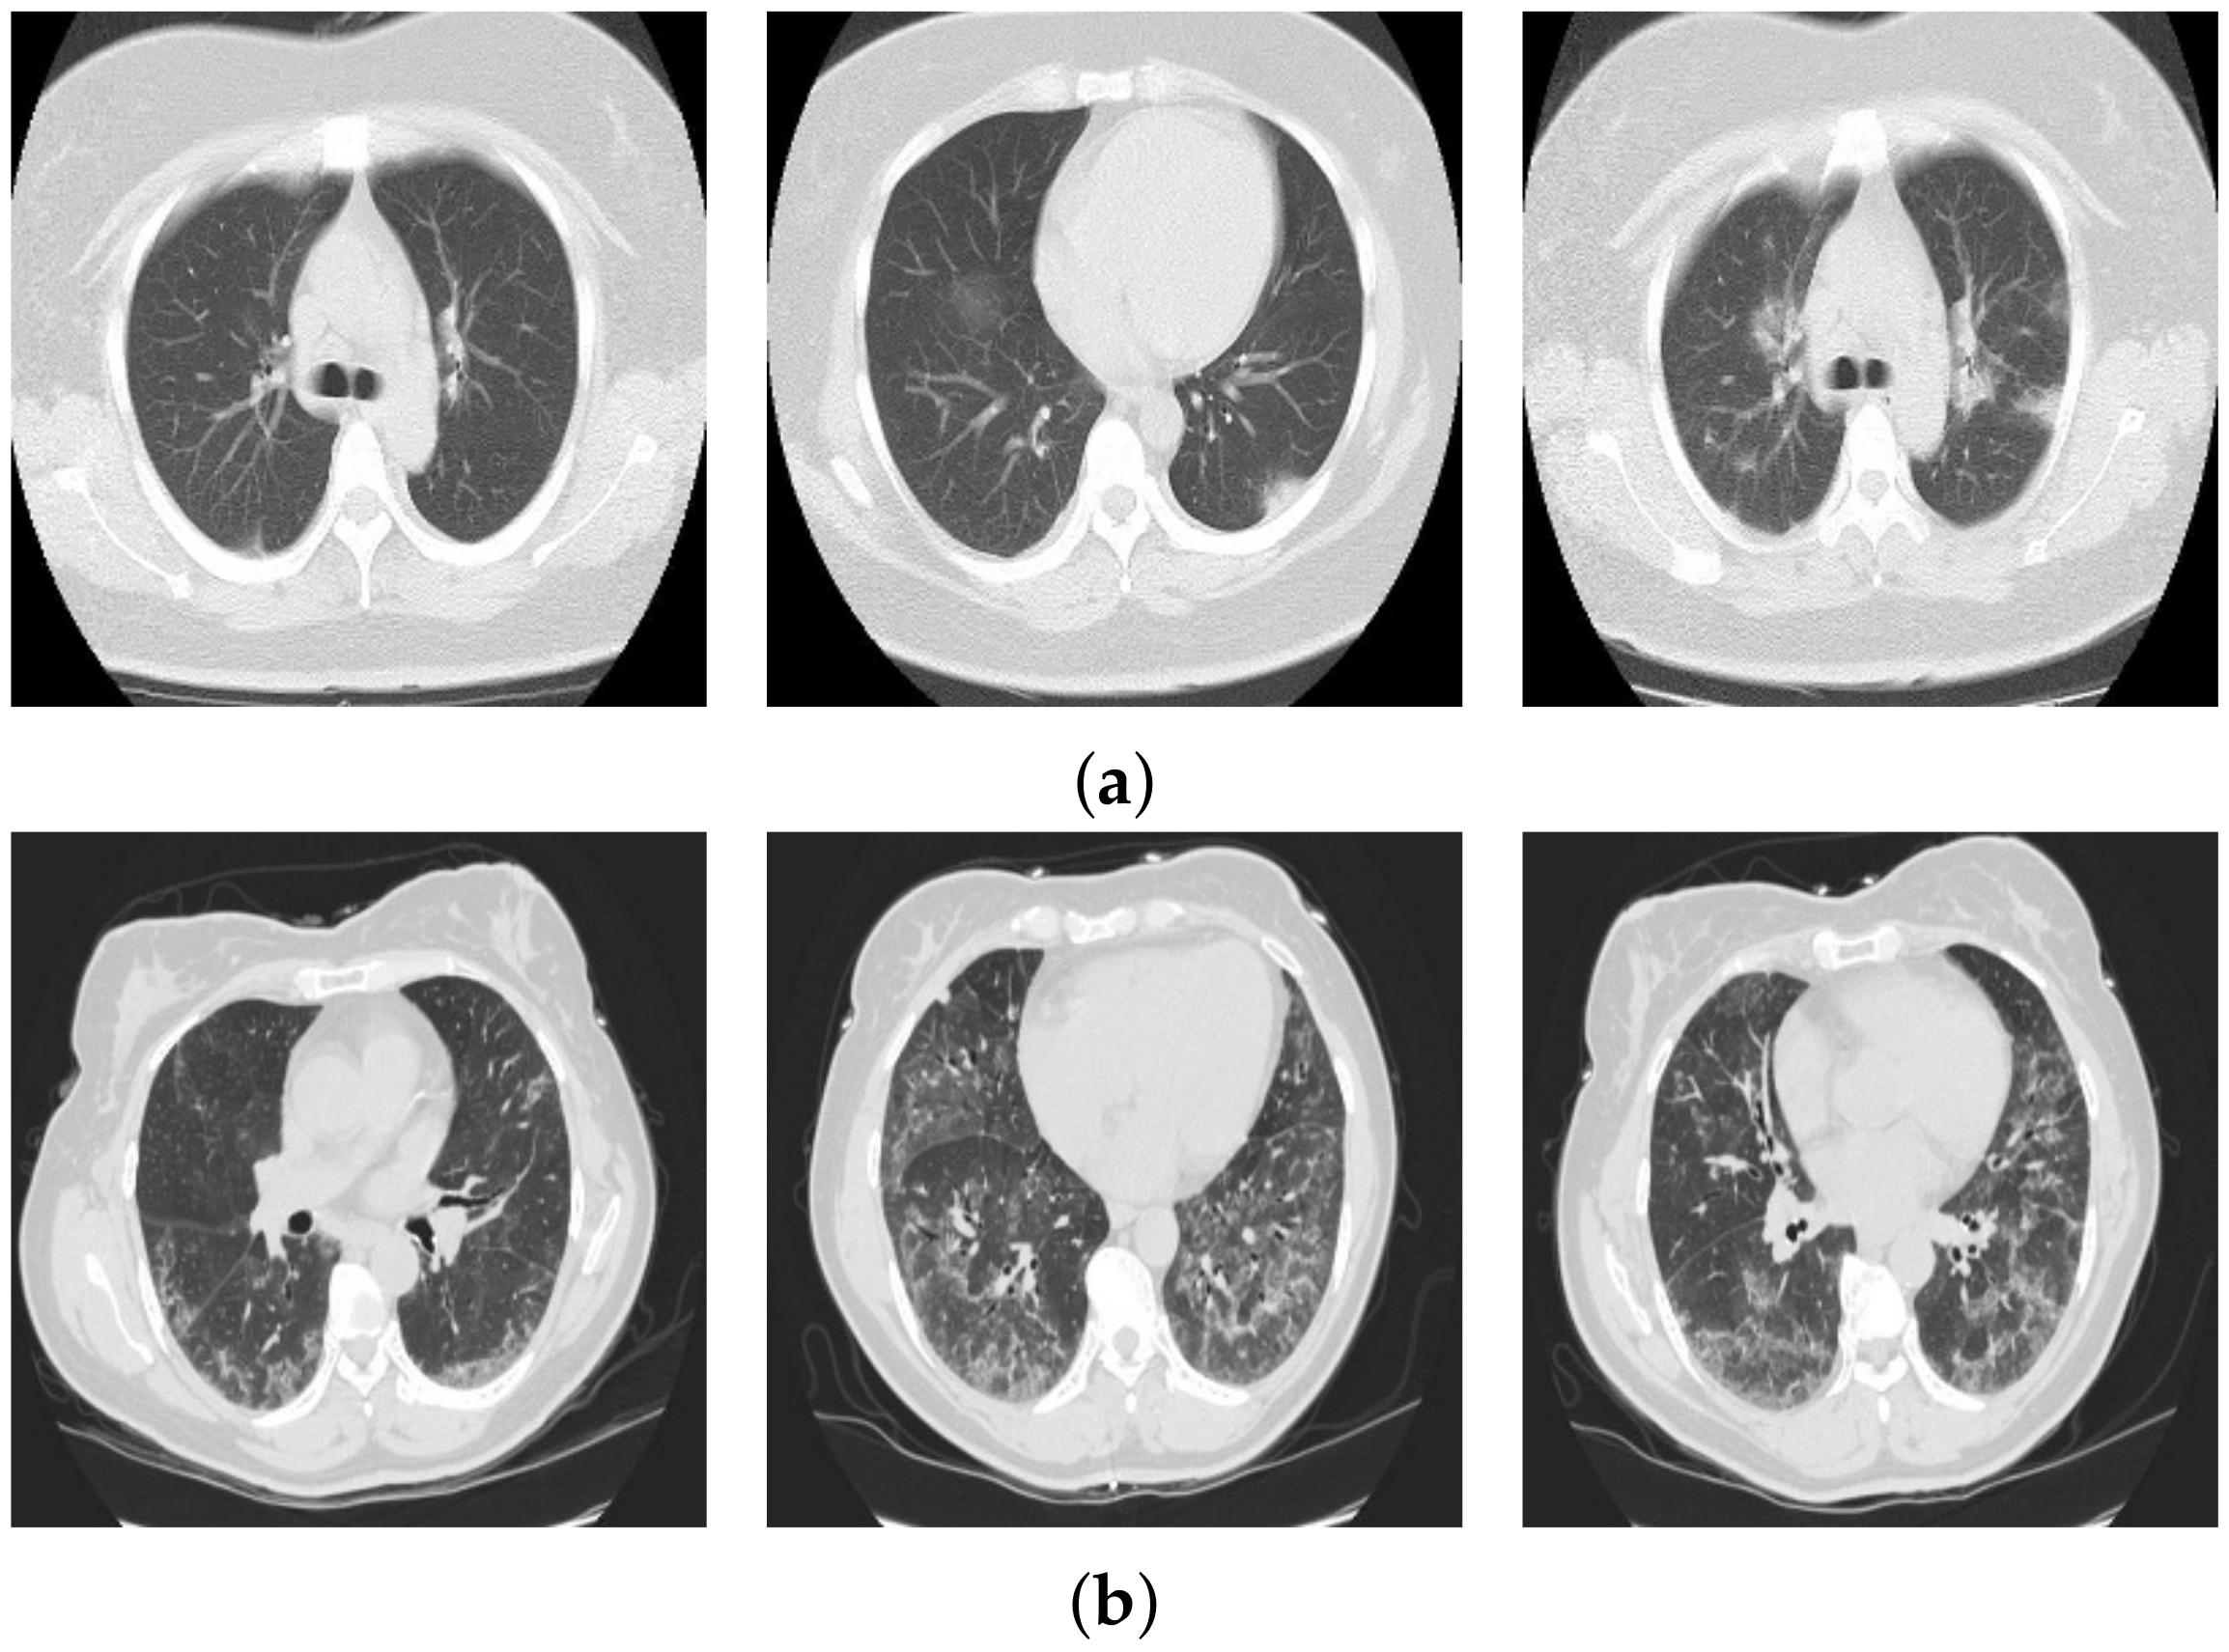

3.1. COVID19-CT Database

3.2. Mosmed Database